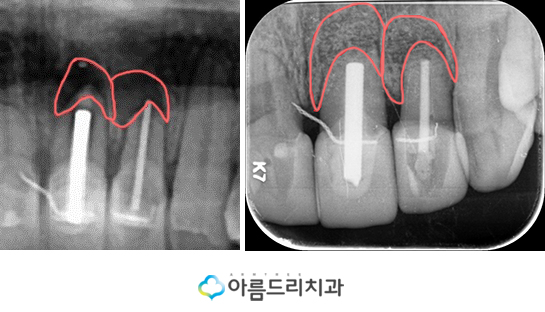

그렇다면 이제 치근단절제술 후 치아의 뿌리 부분이 어떻게 변화되었는지 살펴볼께요.

왼쪽사진이 전 사진이고 오른쪽 사진이 후 사 진인데요. X-ray 상으로 볼때에도 그전에 염증 으로 인하여 검은 부분이 사라지고 정상으로 다시 돌아온 모습을 확인하실 수 있습니다.